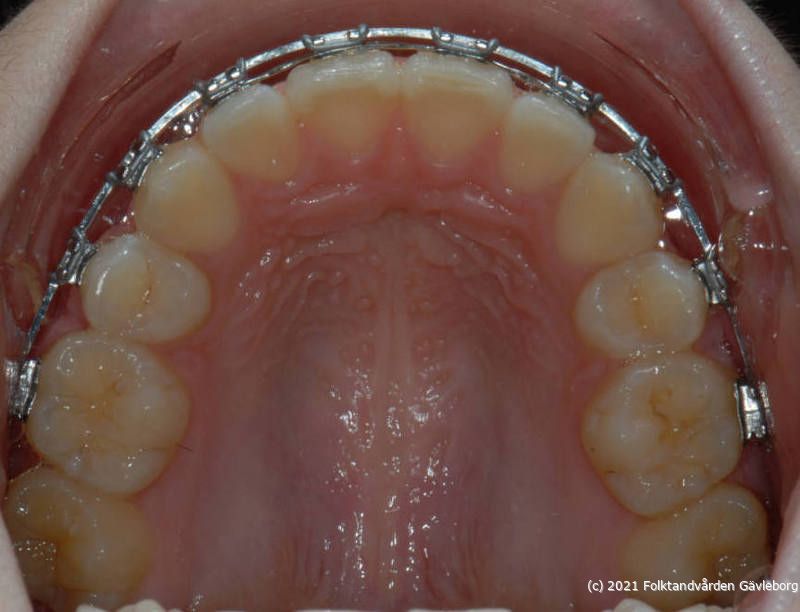

På ortodontiklinikerna diagnostiserar och behandlar vi bettfel på både barn och vuxna. Alla våra patienter kommer på remiss till oss. Vi behandlar bettfelen med fastsittande och avtagbar apparatur. Hos oss behandlas också de patienter som har avvikelser i käk- och ansiktsskelettet och som kräver tandreglering inför rekonstruktiv kirurgi. Vi har ett nära samarbete med allmäntandvård, privattandvård och övrig specialisttandvård i länet samt ett gott samarbete med Akademiska Sjukhuset i Uppsala när det gäller barn med olika syndrom och läpp-käk-gomdefekter. Våra specialistkliniker finns i Gävle och Hudiksvall.

Här nedan hittar du några exempel på vanligt förkommande behandlingar. Hittar du inget som passar det du vill visa, gå in på menyn ovan genom att föra musen över "Information". Navigera sedan till respektive apparatur. Klickar du på rubriken "Visa alla bilder" får du upp samtliga apparaturer som finns här.